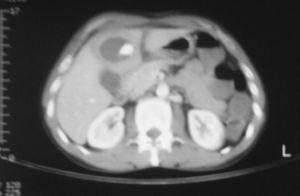

A las pocas horas del ingreso se realiza una tomografía computarizada (TC) abdominal con contraste intravenoso (i.v.) y se evidencia una colección abscesificada en el LHI de 110×90mm con un ribete que no realza con contraste y con impronta en el hilio hepático, lo que ocasiona una moderada dilatación de la vía biliar intrahepática. Se coloca un drenaje percutáneo y se remiten muestras para microbiología y citología (fig. 1).

En sucesivas TC de control se aprecia la disminución progresiva del absceso (fig. 2). Los drenajes se retiran sucesivamente a los 7 y 14 días.